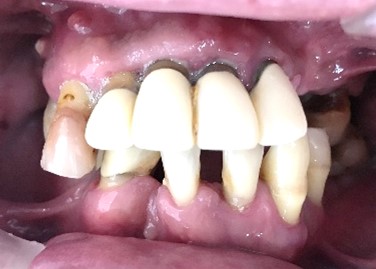

Before

赤丸は抜歯しました

After

【義歯を装着したところ】

【義歯を外したところ】

マグネット式総入れ歯

緑丸は組み込まれたマグネット